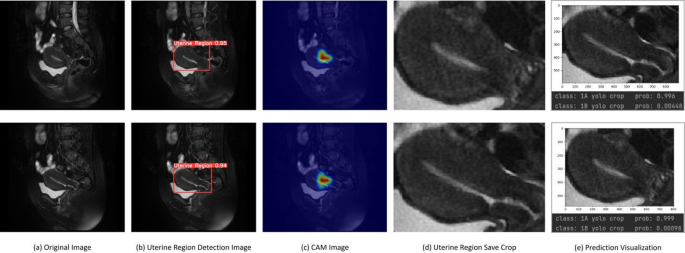

Deep learning models have demonstrated outstanding performance in medical image analysis, but their opacity remains a significant drawback. Due to the complexity and non-linear nature of these models, their decision-making processes are often incomprehensible to humans. To address this issue, this study employs Class Activation Map (CAM) technology to visualize the decision-making process of the model in medical image detection28. As shown in Fig. 7, we present the original image, the uterus region detection image, the CAM visualization, the cropped uterus region image, and the prediction map. CAM highlight the regions of the image that the model focuses on, thus elucidating the rationale behind its decisions and enhancing the interpretability of the model. By visualizing the areas of the image that the model considers important, clinicians can gain intuitive insights into the features the model references during diagnosis. If the regions highlighted by the model align with the clinically significant features identified by the physicians, it indicates a reasonable decision-making process. Conversely, if the model focuses on irrelevant or incorrect areas, it suggests potential biases that need further optimization. Additionally, interpretable models are more likely to gain the trust of clinicians, facilitating their application in actual clinical settings. Therefore, utilizing CAM to visualize the decision-making process of deep learning models not only significantly enhances their interpretability but also improves their credibility in medical image detection, ultimately providing more reliable support for clinical diagnosis and treatment.

CAM maps and the process of staging prediction (a–e).